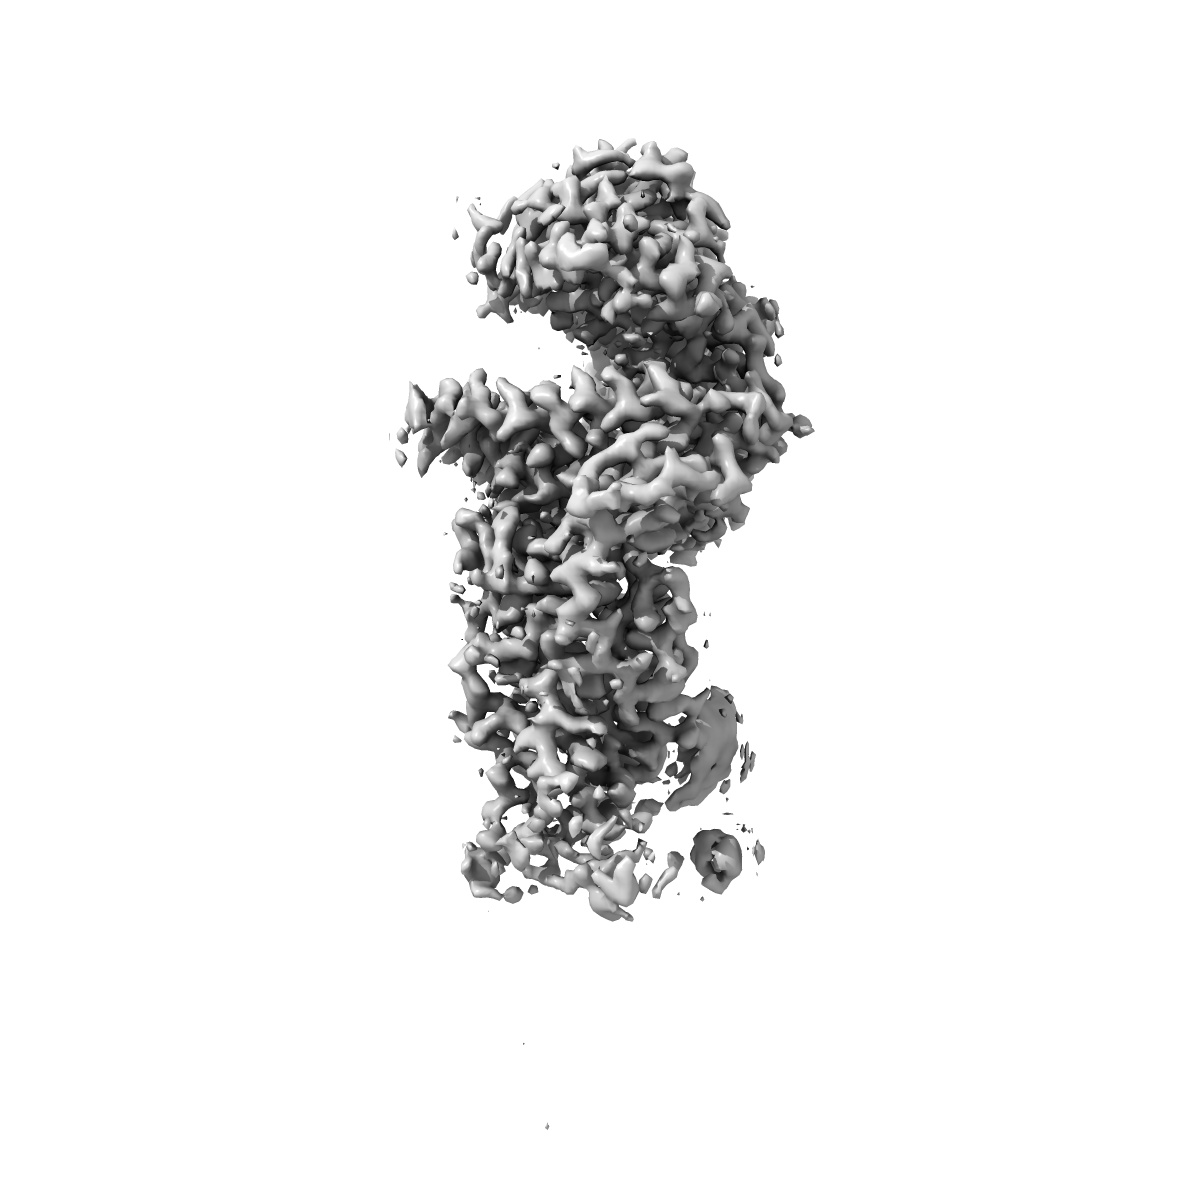

SARS-CoV-2 Omicron Variant RBD complexed with ACE2

Single-particle2.79 Å

Sample: SARS-CoV-2 Omicron Variant RBD complexed with ACE2

Structures of the Omicron spike trimer with ACE2 and an anti-Omicron antibody.

(2022) Science , 375 , 1048 - 1053